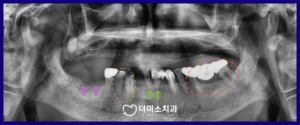

정밀한 검사를 위해

파노라마 사진을

촬영해 보았더니

✅️ 초록색 화살표 표시의

아래턱 양측 첫 번째 앞니는

치주 질환과

맞지 않는 위턱 틀니로 인해

치아가 위로 솟구쳐 올라와 있고

위아래 교합이 맞지 않는 상태였으며,

✅️ 노란색 동그라미 표시의

아래턱 오른쪽 첫 번째 작은 어금니(#43)과

송곳니(#33)는 우식이 심하고,

✅️ 빨간색 동그라미 표시의

아래턱 왼쪽 브릿지 보철물의 치아는

치주가 좋지 않았습니다.

또한 ✅️ 보라색 화살표 표시 부분은

치아가 상실된 상태였는데요.